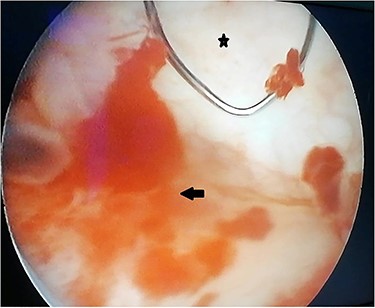

A 55-year-old, nonsmoking patient with no medical or surgical history who had a pulmonary adenocarcinoma diagnosed 1 month prior was referred to the urology department for macroscopic hematuria. Actually, the patient had initially presented with hemoptysis and a computed tomography (CT) scan revealed a right lower lobar pulmonary nodule, which biopsies concluded to a moderately differentiated adenocarcinoma. Interrogation revealed urinary frequency, urgency and several episodes of intermittent hematuria for 3 months. Physical examination showed a patient with an impaired general condition, without other abnormalities and a normal urine color. The urine dipstick revealed a hematuria at two crosses. The biological workup showed no abnormalities and the prostate specific antigen (PSA) level was at 2 ng/ml. The thoracic-abdominal-pelvic CT scan, performed for his lung cancer, showed, in addition to the lung mass of the right lower lobe with a right mediastinal adenopathy, a thickening of the bladder wall enhancing on the right lateral wall, an upper urinary tract free of any lesion and no distant metastases (Fig. 1). Cystoscopy under locoregional anesthesia was performed, showing a normal endoscopic appearance of the urethra and prostate gland, with inflammatory and bullous lesions on the bladder trigone and right lateral wall, which were biopsied using a resector (Fig. 2).

Peroperative appearance during cystoscopy before resection. Star: healthy bladder mucosa. Arrow: bullous inflammatory lesion that was resected.

Cystoscopy shows variable, nonspecific appearances and may even suggest a primary bladder tumor [9]. However, the most frequently described appearance is a single lesion, in contrast to our case [3]. Since tumor proliferation starts deeper to the mucosa, cystoscopy may be normal, especially in the absence of hematuria [8].